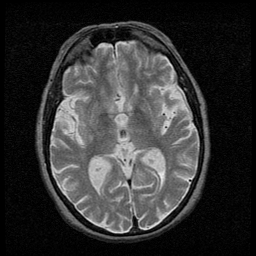

Huntington's Chorea, MR -- Slice #9

[Home][Help][Clinical] Slice 9